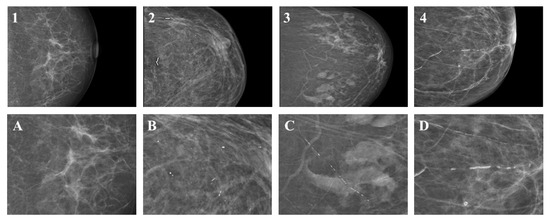

- The classification of breast calcifications into (1) visible or sporadically scattered microcalcifications, (2) suspicious microcalcifications indistinguishable from breast arterial calcification, (3) minor breast arterial calcification, and (4) major breast arterial calcification is feasible with substantial inter-rater agreement and may improve patient management.

2.4. Definitions and Score Generation